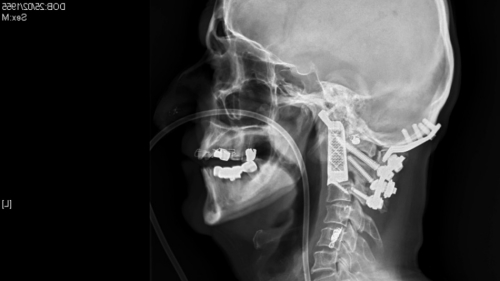

中新网2月26日电 据外媒报道,人体器官移植频传福音,3D打印再写医疗新里程。澳大利亚医生为一名患了癌症的男子进行一项全球第一例手术,替他移除被癌细胞严重破坏的椎骨,再为他植入一条用3D打印技术打印出来旳椎骨。该病人现时康复的进展良好,重获新生。

据报道,病人约塞夫斯基患了脊索瘤,是一种十分罕见的癌症。癌细胞攻击他的脊椎和头骨,并在他的颈项上方位置生长,令他饮食和说话都有困难。医学界估计,每100万人当中,只有一人患上这种病。

去年12月,神经科医生莫布斯为他进行长达15小时的手术,移除本来的椎骨,植入3D打印的脊骨。

莫布斯称,“如果不动手术,又不进行其他针对肿瘤的治疗话,这名病人的情况会转坏,甚至会有死亡的危险。”他说,再拖下去,约塞夫斯基的手脚也会无法活动,甚至会逐渐丧失呼吸的能力。

莫布斯形容手术过程极之复杂和艰辛。手术开始之前,他也无法确定约塞夫斯基是否能保住生命。手术最终取得成功,令他和病人的家人都松一口气。

如今已经两个多月过去了,约塞夫斯基的恢复情况相当不错,他的脖子已经能够活动,不过现在吃东西和说话还有问题,估计还要几个月才能痊愈。